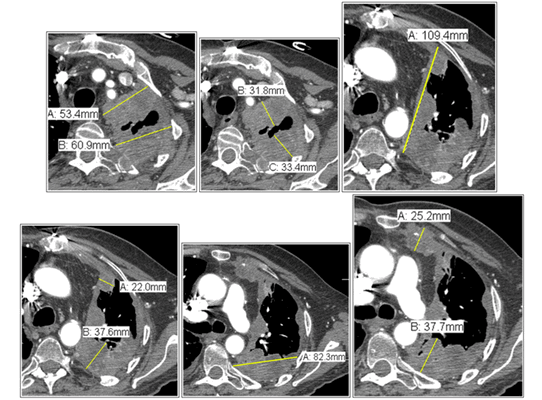

Представлена разница измерений при использовании критерий RECIST и mRECIST.

Слева представлены разница измерений при оценке ответа на проведённую терапию, используя критерии RECIST 1.1 и mRECIST для злокачественной мезотелиомы плевры.

Рекомендации по измерению согласно mRECIST нужно оценить толщину плевры на 3 разных по глубине аксиальных срезах в 2 противоположных сторонах, а после сложить данные 6 показателей следующим образом.

Слева представлены разница измерений при оценке ответа на проведённую терапию, используя критерии RECIST 1,1 и mRECIST для злокачественной мезотелиомы плевры.

Рекомендации по измерению согласно mRECIST нужно оценить толщину плевры на 3 разных по глубине аксиальных срезах в 2 противоположных сторонах, а после сложить данные 6 показателей следующим образом общий размер равен 3.2 + 3.3 + 2.2 + 3.8 + 2.5 + 3.8 = 18.8 см.

Измерение лимфатических узлов

На схеме a и b представлены примеры измерения горизонтально и вертикально расположенных лимфатических узлов, как Вы заметили измерение лимфатического узла производится по короткой оси.

На постконтрастной КТ (изображение C) представлен лимфатический узел субкаринальной группы, усиливающийся постконтрастно, в коротком измерении который составляет 33.4 мм.

Соответствено, согласно RECIST общий размер к двум длинникам нужно прибавить короткое измерение лимфатического узла, тогда общий размер составит (10.9 + 8.2 = 19.1 см) + 3.3 см = 22.4 см,

а согласно mRECIST к 6 показателям измеренной плевры прибавить короткое измерение лимфатического узла, и в данном случае общий размер составит (3.2 + 3.3 + 2.2 + 3.8 + 2.5 + 3.8 = 18.8 см) + 3.3 см = 22.1 см